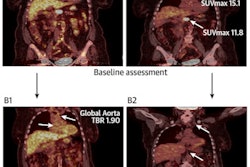

FDG-PET/MRI achieved sensitivity and specificity greater than 95% for cancer detection and sensitivity of 83% and specificity of 100% in determining early postchemotherapy treatment response among 24 patients, essentially mirroring the proficiency of FDG-PET/CT.

In regard to staging, FDG-PET/CT detected 141 positive nodules (20%) from the 696 sites anomalies, compared with FDG-PET/MRI, which discovered 135 true-positive sites (19%). In addition, FDG-PET/CT reported 560 true-negative results (80%), compared with 551 true-negative findings (79%) for FDG-PET/MRI. The results proved to have no statistically significant difference.

Coronal short tau inversion-recovery (STIR) (A), FDG-PET (B), and FDG-PET/MRI (C) fused images show how the hybrid modality detected right supraclavicular fossa and right paratracheal lymphadenopathy, as well as a right lung nodule (arrows), in a 14-year-old male with Hodgkin lymphoma. Images courtesy of the Journal of Nuclear Medicine.As for response assessment, FDG-PET/CT spotted six true positives (0.9%), which would indicate an incomplete treatment outcome, among a total of 609 disease sites. By comparison, FDG-PET/MRI detected five of those six true positives (0.8%), with one incomplete treatment response missed due to a "perceptual error." When the researchers corrected for that miscue, they achieved "perfect agreement" for staging and "excellent response assessment agreement" between FDG-PET/MRI and FDG-PET/CT, they added. Again, there was no statistically significant difference.

"In our cohort of patients, FDG-PET/MRI showed no difference in overall staging compared to FDG-PET/CT for staging of Hodgkin lymphoma in children and adolescents, and there was excellent response assessment agreement," the authors concluded. "With the aim of reducing cumulative radiation dose, we suggest that pediatric/adolescent Hodgkin lymphoma staging and response assessment may be performed using FDG-PET/MRI instead of FDG-PET/CT, wherever possible."